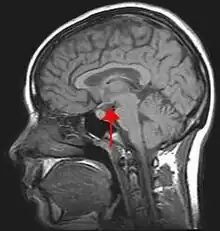

Hypothalamus

NSC \ɛn.ɛs.se\ masculin singulier invariable

- (Anatomie) Noyau suprachiasmatique.